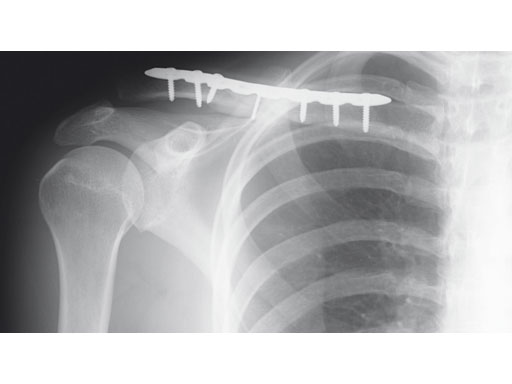

A 22-year-old man sustained an open clavicle fracture after a motorcycle injury.

Fig 2ab Postoperative images.

Fig 3ab X-rays taken 3 months postoperatively.

Case provided by Harry A Hoyen III, Cleveland, USA